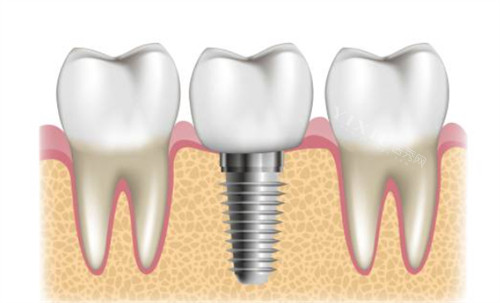

作为院内核心项目,种植牙价格涵盖主流植体品牌,满足不同预算与修复需求,所有价格均包含植体、基台及基础牙冠(全瓷牙冠需额外补差价):

韩国登腾:5999 元起(适合单颗牙缺失,性价比之选,使用寿命可达 10-15 年)

韩国奥齿泰:6599 元起(植体稳定性更强,适配牙槽骨条件中等患者)

美国皓圣:8999 元起(即刻种植适配性高,术后改善周期缩短 30%)

德国 ICX:9699 元起(钛合金材质耐腐蚀,适合多颗牙缺失连桥修复)

德国 Camlog:11800 元起(个性化基台设计,兼顾功能与美观,适合前牙种植)

瑞士 ITI 标准款:13800 元起(亲水表面技术,骨结合速度快,适合牙槽骨较薄患者)